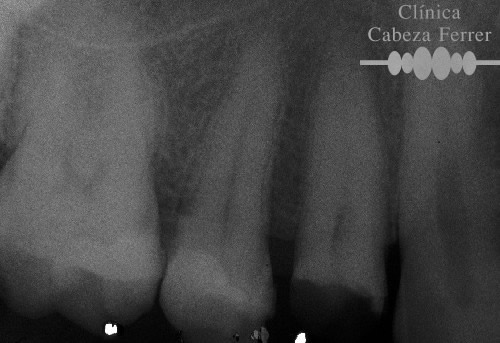

| Antes | Después |

En primer lugar se explora la pieza y se realiza un estudio radiológico. Si es necesario se pone anestesia local y se aísla en diente para mantenerlo limpio y seco durante el tratamiento. A continuación con el instrumental adecuado se realiza un orificio en la corona del diente y a través de él, mediante unos pequeños instrumentos llamados LIMAS, se extrae la pulpa. Posteriormente la cámara pulpar y los conductos radiculares se limpian, se esterilizan, se rellenan y se sellan herméticamente. Con un control radiológico se comprueba que el tratamiento se ha realizado correctamente. Ahora es el momento de reconstruir la anatomía del diente y si es necesario recubrirle con una corona para evitar su posterior fractura. En la mayoría de los casos, la endodoncia se realiza en una sola sesión.